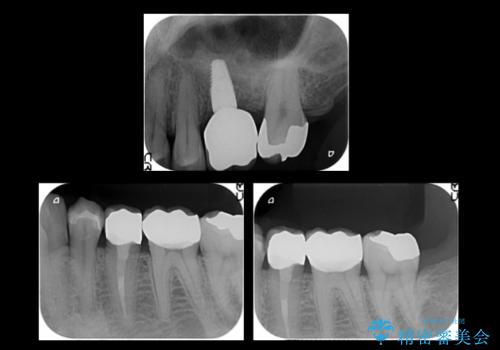

インプラントの向かい合わせの歯や隣の歯の虫歯治療も併せて行なっています。

同時期に治療することで咬み合わせの調整がしやすく、また、適合の良いものを作成できるメリットがあります。

左上6:インプラント(ストローマン)20万円、カスタムアバットメント10万円、スクリューリテイン仮歯2万円、ジルコニアクラウン10万円、ソケットリフト10万円、マイナーGBR 5万円、静脈麻酔(麻酔認定医)5万円

左上7・左下7:PGAインレー 各6万円

左下5:仮歯 1万円、ジルコニアクラウン10万円、ファイバーコア 2万円

左下6:仮歯1万円、ジルコニアクラウン10万円